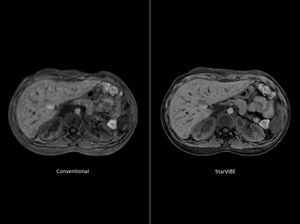

Unfortunately, uncooperative patients cannot hold their breath. The new sequence from @siemens that called STAR VIBE (Radial VIBE), provides radial k-space sampling in a fully seamless way, aiming at achieving higher robustness to motion and flow effects in daily practice. The STAR VIBE sequence can yield images of comparable image quality with conventional breath hold VIBE sequence at the expense of longer acquisition time.